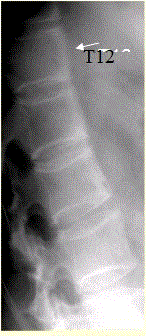

问题 患者男,35岁,外伤后行腰椎CR检查,结果如下图。 观察所给出的MRI图像(下图),你的判断为

选项 A.椎体边缘多发T1WI、T2WI高信号影,考虑为椎间盘退变所致椎体终板改变II型 B.椎体前部上下缘的韧带下骨炎 C.L1~2、L3~4椎间盘信号异常,考虑为椎体结核 D.L1~2、L3~4椎间盘信号异常,考虑为椎体化脓性炎症 E.腰椎退行性改变 F.类风湿性关节炎累及椎体 G.强直性脊柱炎

答案 BG